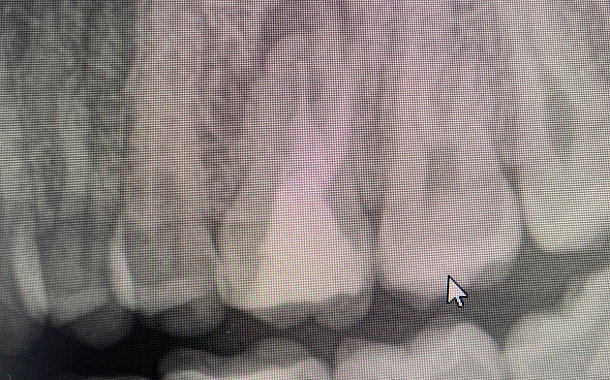

По 3D компьютерной томографии определяет возможность установки имплантата, немедленной фиксации временной коронки в день операции и объем пластических манипуляций. Совместно с врачом-стоматологом ортопедом планирует вид ортопедической конструкции и положение имплантата.

Компьютерная томография в формате 3D - важный диагностический инструмент стоматолога. На полученном объемном снимке стоматолог видит все нюансы вашей зубочелюстной системы: состояние костной ткани челюстей, зубов и височно-нижнечелюстного сустава. Именно томография позволяет доктору составить план и объем предстоящего оперативного вмешательства.